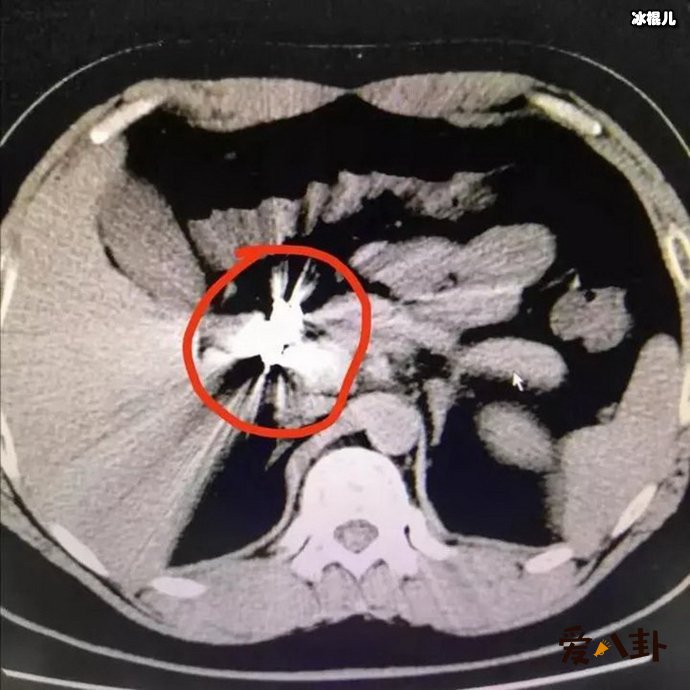

但是小柯的回答让医生也吓了一跳,他回答称:因为自己与女朋友吵架,在吃金项链之前,还赌气吃了200颗的褪黑素下去。这可让医生吓了一跳,马上安排给小柯做相关的检查,发现金项链已经到了肠子里了,而小柯也没有什么不舒服的地方。因此,医生表示金项链会随着大便一起排出,建议小柯在回家排便的时候注意看一下金项链有没有排出。